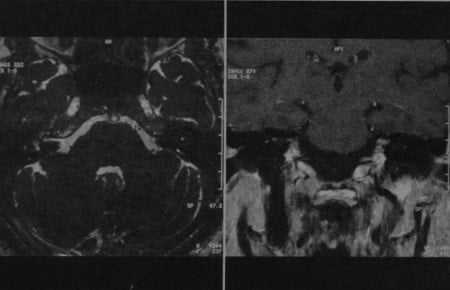

Усиление по ходу лицевого нерва после введения гадолиния у мальчика 15 лет с остро возникшим невритом правого лицевого нерва.

CISS-последовательность: незначительный отек канала лицевого нерва. Фронтальная проекция: выраженное усиление лицевого нерва в его канале.